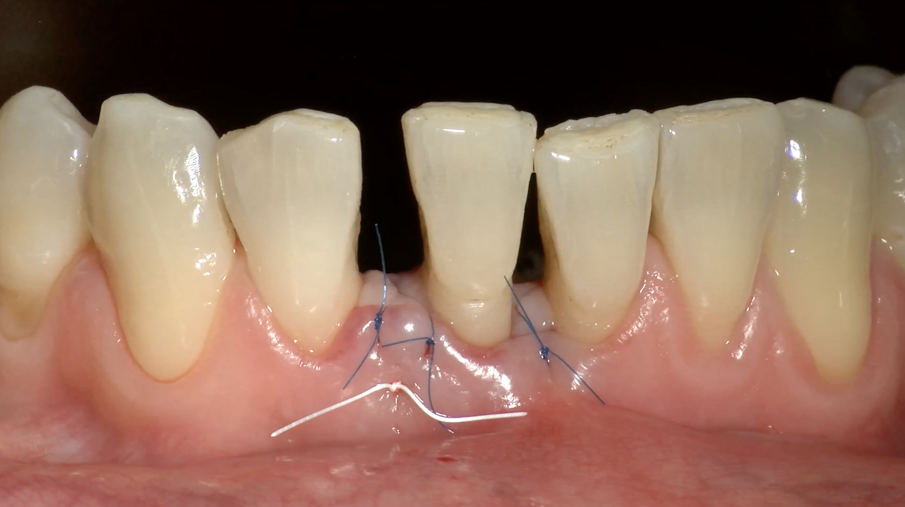

Fig. 6g - Lembo suturato.

Il lembo stesso è stato suturato con un punto a materassaio verticale in e-PTFE e con punti singoli in Prolene 7.0 a livello delle due papille distale e mesiale (Fig. 6g).

Il Paziente veniva premedicato con Zitromax 500 mg e Ibuprofene 400 mg. Eseguita anestesia loco regionale con articaina 1:100.000 con adrenalina veniva sollevato un lembo muco periosteo a spessore totale con tecnica di preservazione di papilla MPPT (Cortellin i 1995) e incisione intrasulculare (Figg 6d, 6e). Il difetto in sede interprossimale e vestibolare è stato degranulato con ultrasuoni e curette manuale. Raggiunta la perfetta decontaminazione del sito è stata preparata la barriera GUIDOR matrix barrier partendo dalla configurazione specifica per difetti interprossimali (DC double curved) in modo da renderne corretta la dimensione mesio distale e apico coronale (Fig. 6f) .